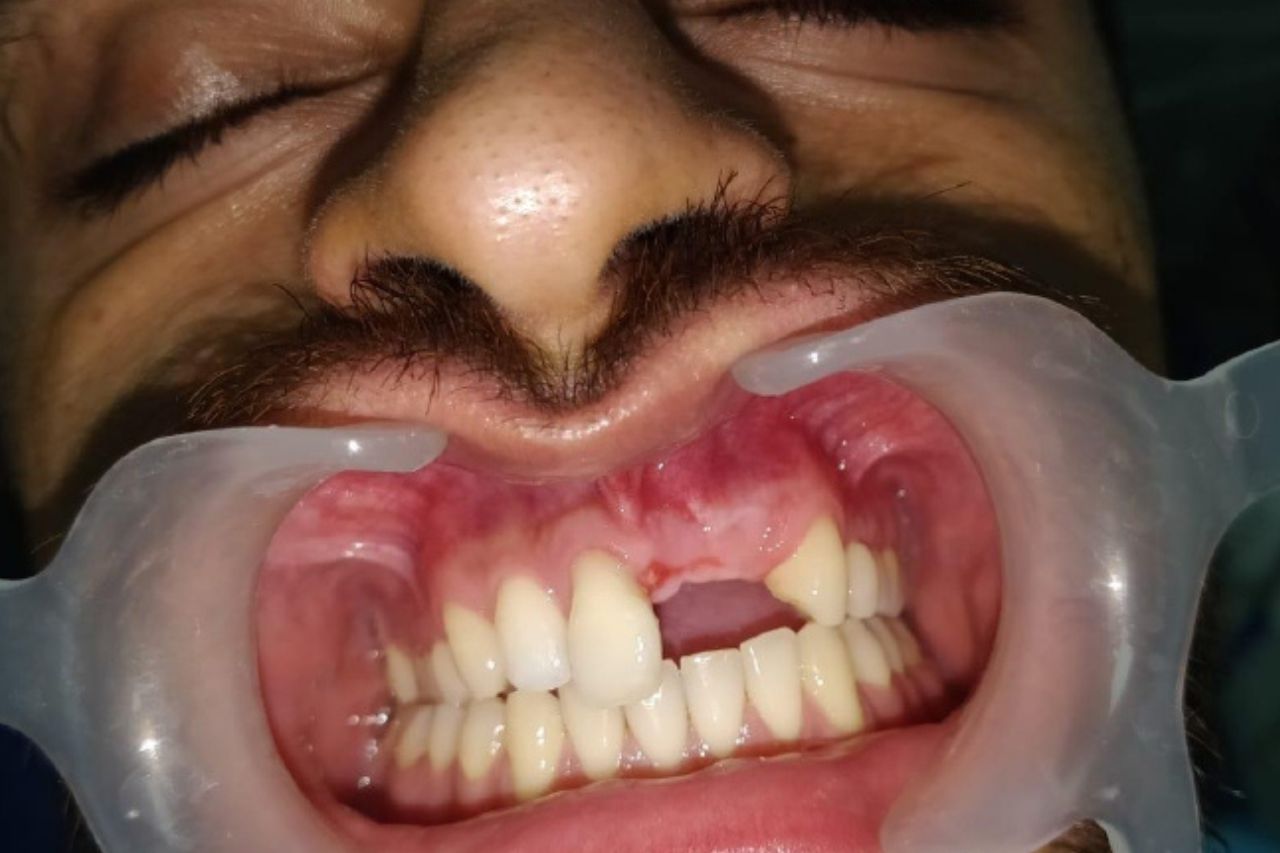

No one can predict the future. In fact, sometimes life throws such hurdles in our path that we don't know how to handle them. Something like that happened with this 25-year-old boy. He met with an accident post where he lost some of his teeth.

This was a major setback as his entire appearance changed. People noticed it and passed insensitive remarks that really upset him.

That is when he came to know about Smriti Raj Dentistry . He decided to take this life-changing decision and opted for the Guided implant surgery. Dr. Raj saw that the situation was rather grave. He handled the case rather tactfully to ensure the results were as per expectations.

Dr. Raj Tiwary suggested that the boy opt for guided implant surgery. This procedure is pretty accurate, and the results are also amazing. Since the dentist can check the status of the implant at every step, the chances of success remain very high. Also, the implants can be customised as per the client's requirements.

The entire situation was discussed with the boy and his family. They were shown the results of previous cases, and considering the high success rate, they agreed to the surgery. A CT Scan was conducted, and images of the damage done were taken.

Now came the real task of inserting the implants. After regular appointments, the implants were carefully placed, and the boy was informed about any precautions that were required. The results impressed the boy, and he could not contain his happiness.

Due to Dr. Raj's careful care and guidance, an impossible dream has been fulfilled. The boy went back with renewed confidence, and his friends and relatives were astonished to see the transformation.